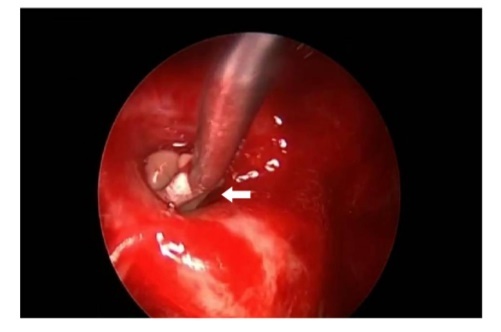

A 64-year-old lady presented to the outpatient department with complaints of headache and right eye blurring of vision for one month. Neurological examination revealed that bitemporal hemianopsia and impairment of visual acuity. Findings from fundus examination were within normal limits. Rest of the brain appeared unremarkable. Endocrine evaluation was normal. Results of renal function tests, liver function tests and haemogram test were within normal limits. A clinical diagnosis of non-secretory pituitary adenoma was made. Magnetic resonance imaging showed a well-circumscribed contrast-enhancing lesion in the sella (Figure 1, Figure 2). The patient underwent an endoscopic endonasal/transsfenoidal surgery in the supine position and total lesion resection was peformed. Intraoperatively, the lesion was found to be yellow colour, soft and avascular and it was removed totally until the sella turcica was visualized (Figure 3).In histopathologic examination septate hyphae were observed between inflammatory cells, Grocott staining is positive, but acid-fast stain for acid-fast bacilli (AFB) was negative. Histopathological findings suggest that infection of Actinomyces (Figure 4, Figure 5). We performed to patient consulted by patients to infectious diseases clinic. Patients underwent intravenous 6x2 gr ampicillin for four weeks.Then oral 4X500 mg amoxicillin treatment is planned a for at least 6 months. Patient did not have any deficits in the next six months.

Figure 3.White arrow shows in intraoperative image that the lesion was found as a yellow colour, soft and avascular shape